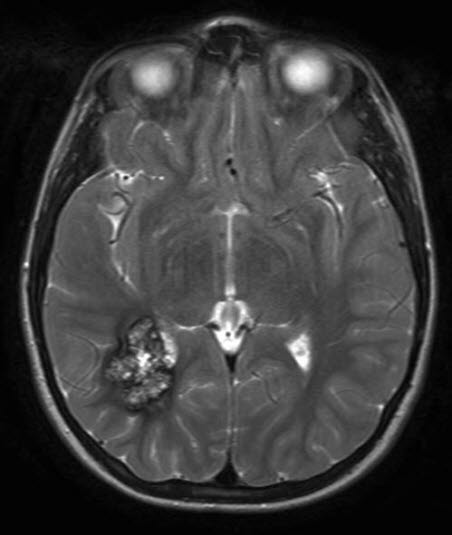

Kavernøst hemangiom, aksialt snitt 2

Gjengitt med tillatelse av Radiologisk avdeling, Universitetssykehuset Nord-Norge